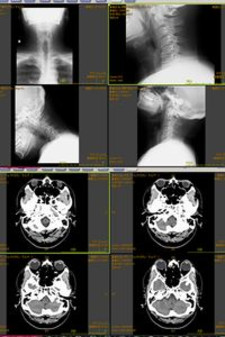

画像は、先日撮影したCTとレントゲンの画像の一部ですが・・・整形外科への紹介状を書いてもらったところ、添付される撮影結果は昔ながらのフィルムではなく、CD-Rにビューワ付きで焼かれていたという・・・

で、病院のミスなのか何なのか、何故か封印されてなかったので、早速isoイメージで保存しておきましたが、医者が診るそのまんまのデータなので、結構興味深いかも?